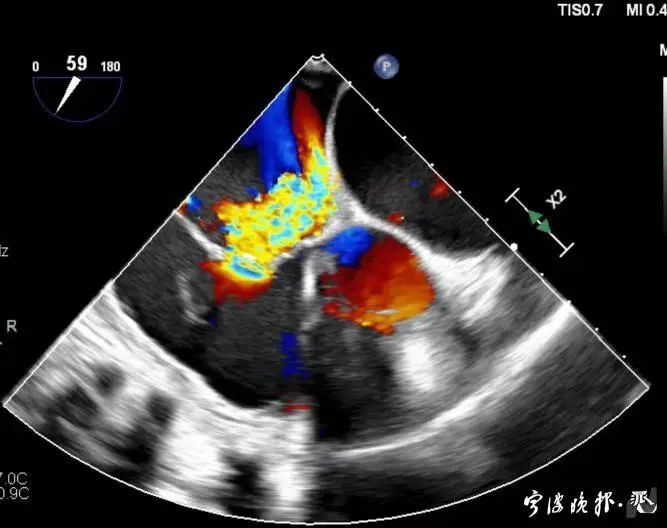

術后食道心超示三尖瓣反流消失